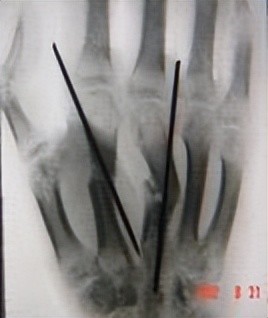

克氏针最基本也是最重要的作用就是进行骨折复位后内固定。当单独使用克氏针时,以儿童肱骨髁上骨折为例,根据患儿年龄及形态,选择合适规格的克氏针,多为1.5~2.0mm克氏针。而在治疗较简单的手部骨折时,克氏针可作为髓内固定,其规格更为细小,对周围软组织基本不产生损伤,远期效果佳。克氏针在治疗足部骨折也有着一定的优势。一项回顾性研究显示,使用多根全螺纹直径1.6mm克氏针治疗跟骨关节内骨折,除1.8%的患者出现针道感染、3.1%的克氏针断裂外,患者总体并发症发生率较低,预后良好。除了起到骨折复位后固定作用外,在治疗足部畸形效果也颇为显著,Kramer等评估了876例应用克氏针固定治疗槌状趾的矫正效果,结果显示治愈率高,临床应用价值颇高。

临床上,克氏针也经常与其它技术联合使用。对于复杂的手部骨折,可在骨折复位后使用直径稍小的克氏针进行固定,联合微型外固定架,使关节内骨折块复位良好,后期配合功能锻炼,基本可全面恢复。其它部位如胸锁关节脱位时,可使用张力带联合克氏针进行复位和固定,效果明显,预后佳,随访的病例均获得良好恢复。除此之外,张力带钢丝联合带螺纹克氏针可在关节镜下治疗胫骨髁间嵴骨折,使用带有螺纹的克氏针固定更为牢靠,有效防止骨块旋转及钢丝脱套。